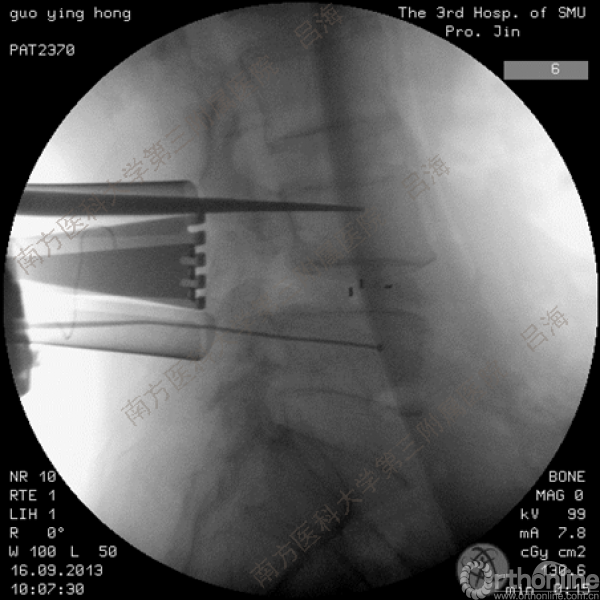

随着社会老龄化进程加快,胸腰椎退行性病变的治疗已经成为脊柱学术界的一个热点话题。MIS-TLIF手术可以治疗多种不同的胸腰椎退行性疾病,南方医科大学第三附属医院吕海教授结合病例为我们一一展示了该术式在治疗不同胸腰椎疾病时的具体手术过程。